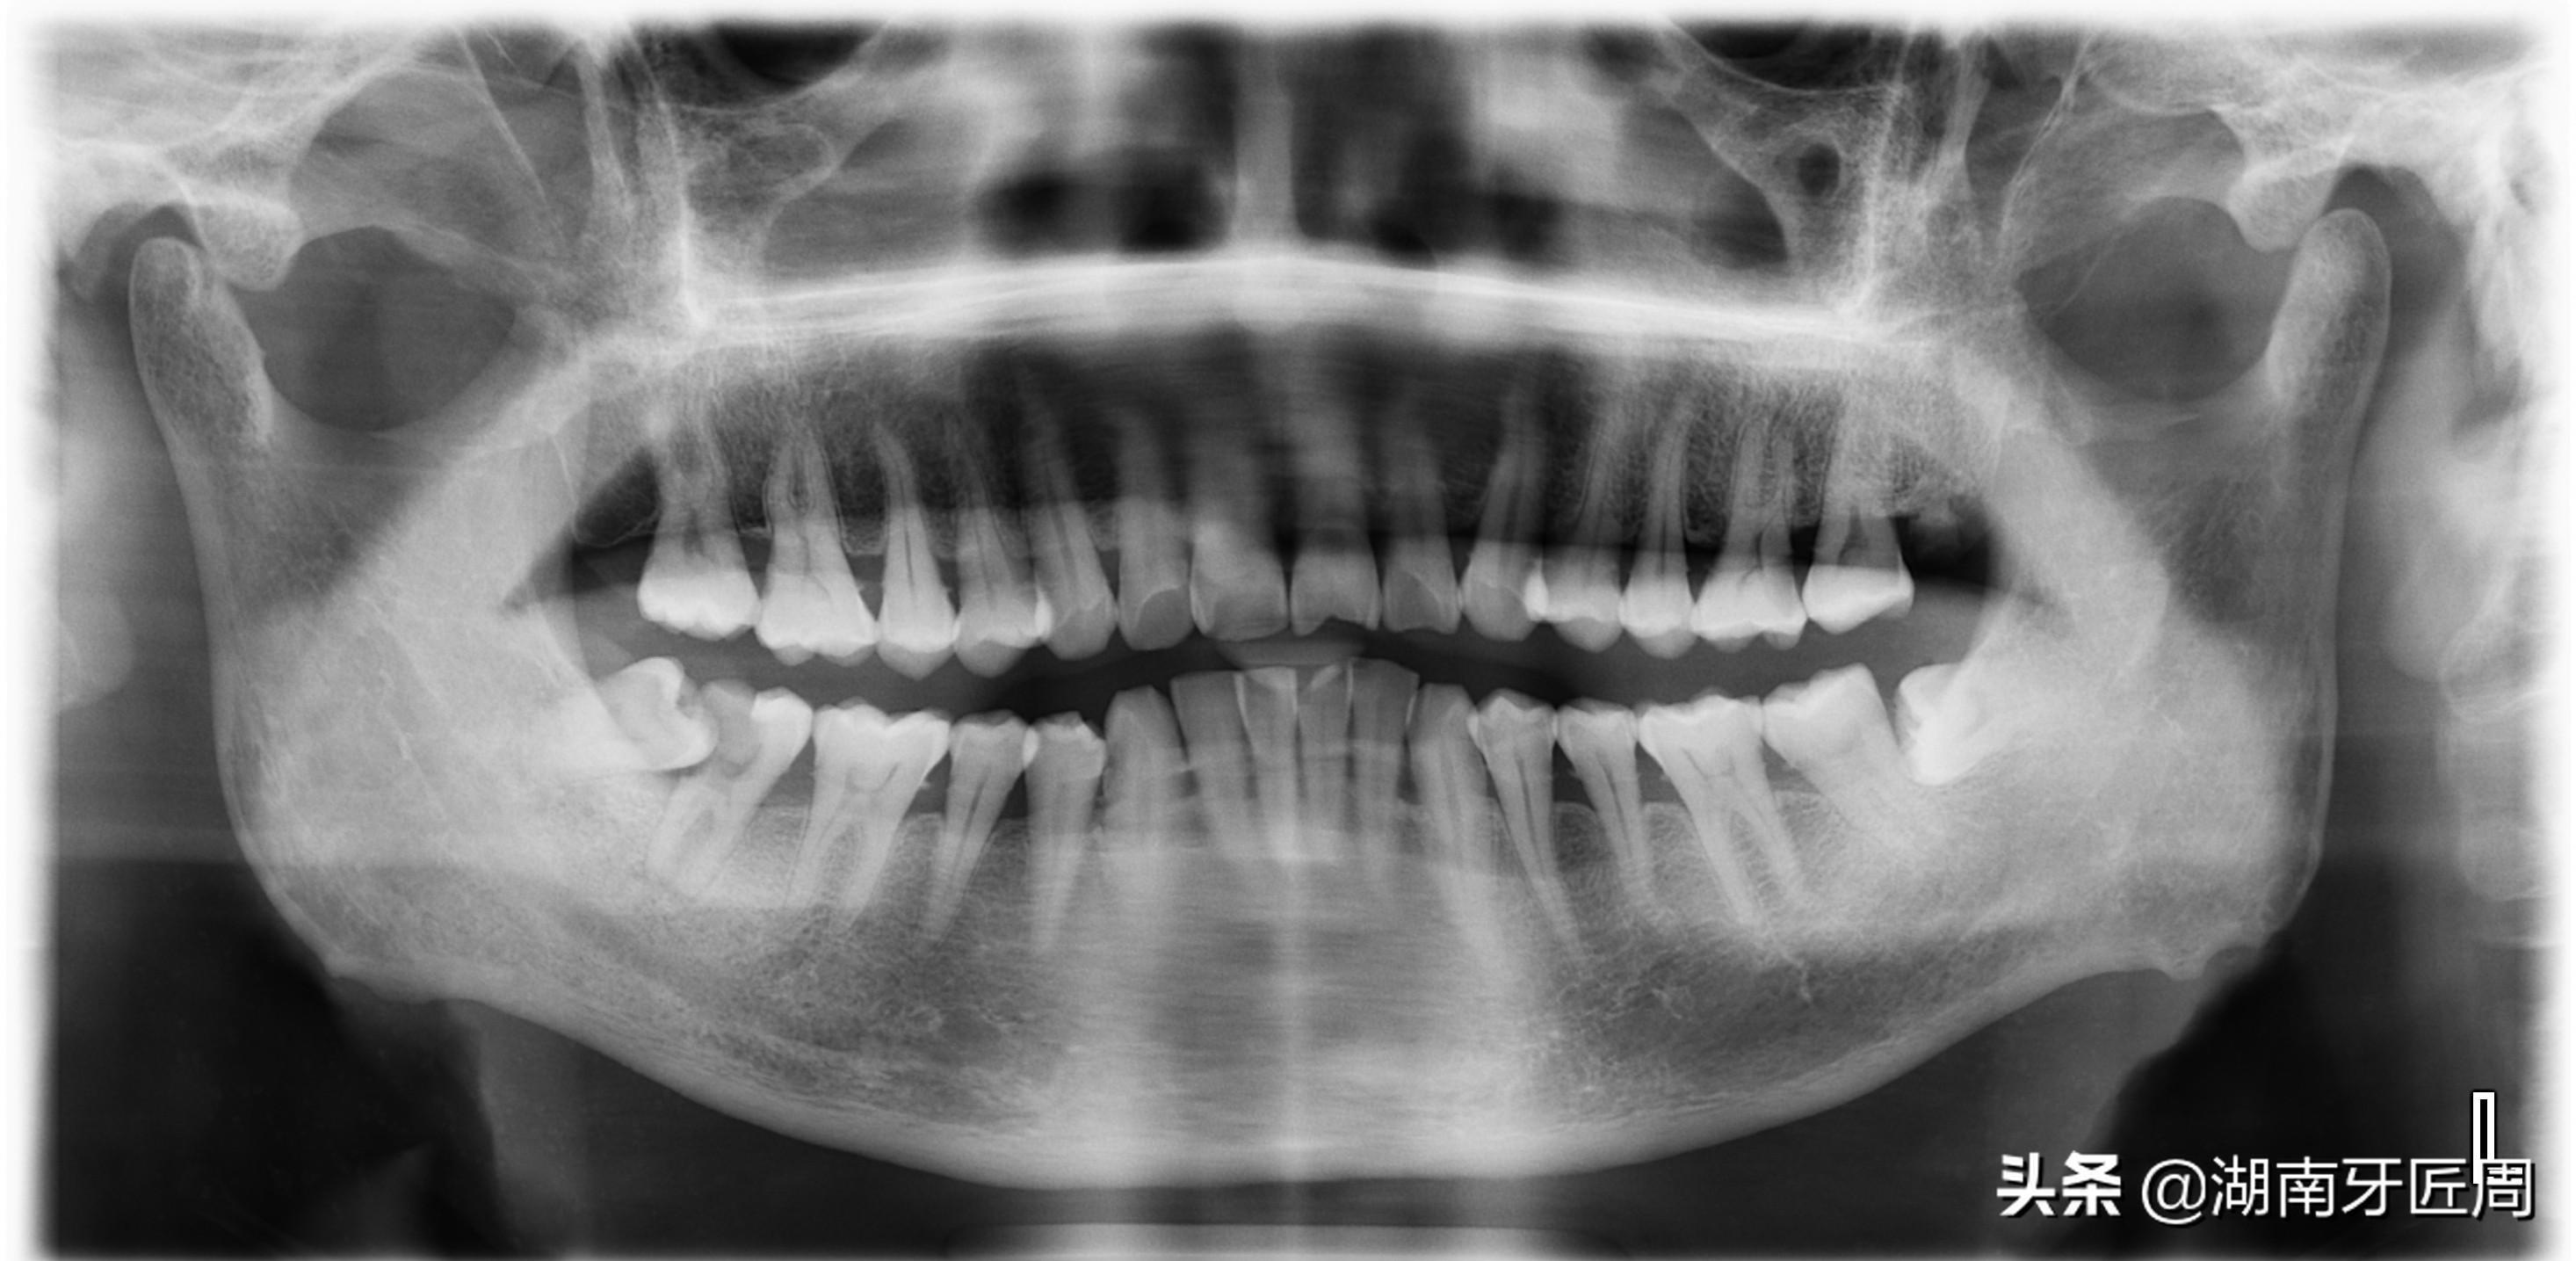

图片5.左侧智齿埋伏水平阻生

图片6.右侧上颌智齿接近水平阻生

图片7两侧下颌智齿阻生